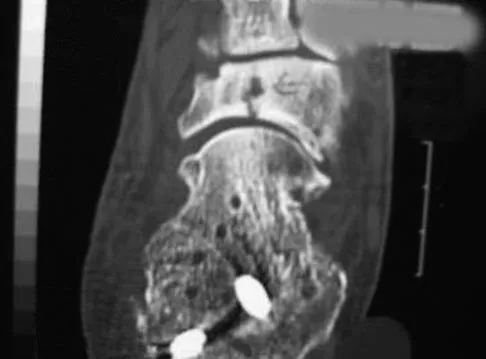

A 21-year-old man has had right groin pain for the past year. A radiograph, CT scan, MRI scans, and a biopsy specimen are shown in Figures 50a through 50e. What is the most likely diagnosis?

Explanation

A 21-year-old man has mild but persistent aching pain in his left proximal thigh during impact loading activities. He denies pain at rest and has no other symptoms. Figures 34a through 34e show the radiographs and T1-weighted, T2-weighted, and gadolinium MRI scans of the left hip. What is the most likely diagnosis?

Explanation